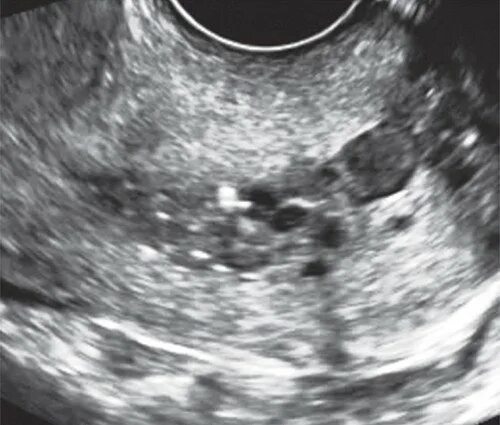

Серозометра лечение